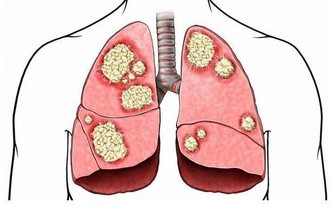

- 一方面,受寒冷刺激,血管收縮,血壓上升快,易增加腦血管意外發生。

- 另一方面,冬日早晨霧氣重,大氣對流緩慢,廢棄無法向大氣層擴散,空氣較為污濁,若此時鍛煉,弊大於利。